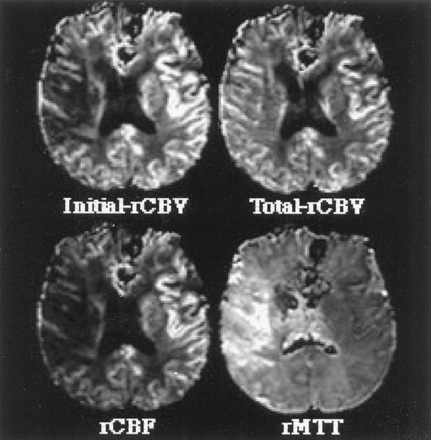

图2。这个图展示了水平切片两种不同脑血容量cb v()都未地图(cb v初始相对[rCBV],都未总rCBV),相对平均运输时间(rMTT)地图,和一个图像代表相对脑血流量(rCBF)。看到更多的细节关于这些图片的方法计算。

之间的各种估计rCBV,最初的操作半影rCBV是最好的预测。最初rCBV反映曲线下的面积曲线的初始部分,因此指数加权的rCBV流入血液的体积。最初rCBV非常类似于rCBF在这项研究中,这中可以看到图2而在表1显示类似的比例差异半影和缺血性核心定义的操作。虽然最初的rCBV显著降低,总rCBV显著增加的运营半影侧控制区域。然而,总rCBV不如最初rCBV差异化运营从缺血半影的核心。rCBV总数的增加在我们的操作半影同意大多数宠物cb v测量显示增加缺血半影中都未引起的早期代偿反应脑灌注压降低。12,13rCBF略优于初始rCBV在区分半影从核心定义的操作。rMTT显著延长操作半影,更在缺血性核心。然而,rMTT是不如其他标记区分从缺血半影核心定义的操作,但在区分异常(即是一个优秀的标志。,核心和半影)从正常灌注(见表1)。